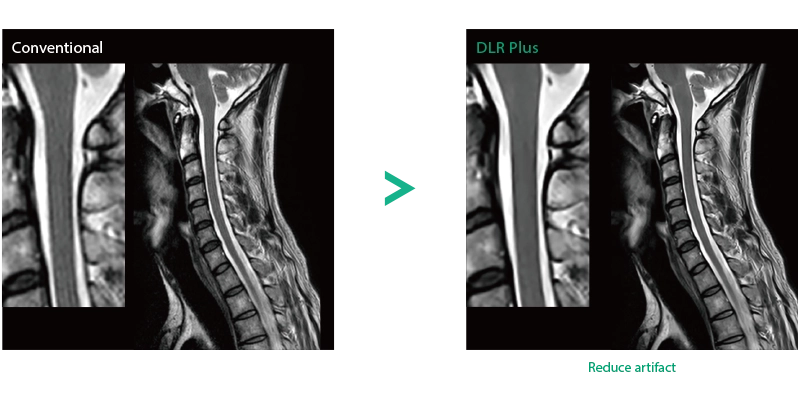

Deep Learning technology*8 enables image quality adjustment after imaging is complete. It optimize SNR and improve image sharpness by processing MRI signals in stages (k-space signal processing). This brings super-resolution and reduces truncation artifacts.

When the size in the phase encoding direction is incorrectly set , the signal outside the FOV will fold back and appear as artifacts in the image. Exp. RAPID reconstructs the image according to the specified FOV magnification ratio. Artifacts can be removed in post-processing.

- *8 Deep Learning is used for the development. The performance and accuracy of the device will not automatically change after installation